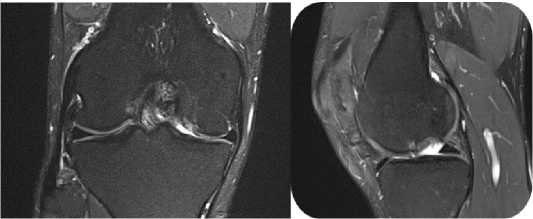

При клиническом осмотре выявлено ограничение объёма движений с амплитудой сгибания–разгибания от 15° до 100°. Симптомы повреждения латерального мениска – отрицательные, однако с медиальной стороны отмечается болевой синдром при проведении тестов Мак-Мюрррея и Апли; признаков нестабильности коленного сустава, а также локальных проявлений воспаления не обнаружено. По данным рентгенографии признаков костно-травматической патологии не выявлено; определяется умеренное сужение медиальной суставной щели. МРТ-исследование выявило хрящевой дефект медиального мыщелка бедренной кости размерами 25 мм × 20 мм (площадь 5 см2) и разрыв в области заднего рога медиального мениска (Рисунок 7).

Рисунок 7 . Изображения снимков фронтального и сагиттального срезов с демонстрацией дефекта в области медиального мыщелка правой бедренной кости